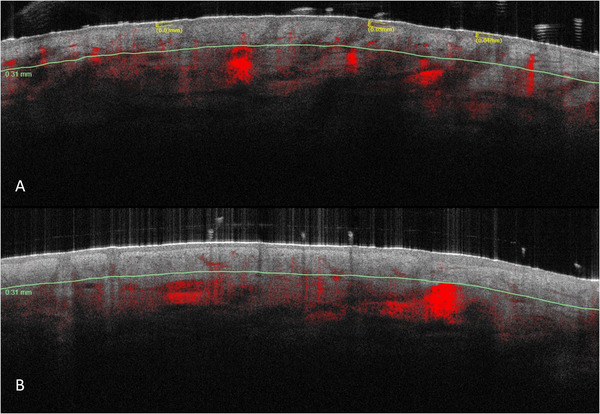

Study objective: The aim of our study was to evaluate the benefits of supplements with an herbal mixture based on Venerinase and B-group vitamins, Zinc, and Magnesium in preventing/reducing photoaging by means of objective quantitative analysis of visual skin features obtained by VISIA 2D and stroma and vascular characteristics measured by Optical Coherence Tomography (OCT).

Results: The treated group showed a significant reduction in the mean Griffith scale score from 4.5 at baseline to 3.76 at T2 (4 months) (p = 0.001). A significant decrease in red areas and a borderline significant reduction in the number of wrinkles have been shown by skin aging objective feature calculation on VISIA 2D photographs. OCT analysis showed a borderline significant reduction in collagen density.

Conclusions: The decrease in vascular pattern and collagen density suggests an anti-inflammatory effect with a potential stromal remodeling in the treated group. This seems to be correlated to the reduction in wrinkles and facial redness.